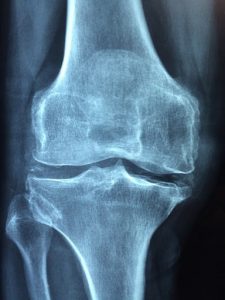

Similarly, X-ray, MRI, and CT scans can also help with the diagnosis. These tests are more conclusive as they can rule out any other possible causes for your symptoms.